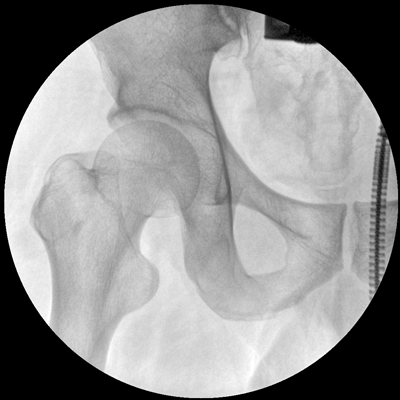

小巧輕便 超凡靈動(dòng) PLX C1116

●一體化機(jī)架設(shè)計(jì),占地空間小,移動(dòng)靈活

●一人獨(dú)立操作,即可完成C形臂的移動(dòng)與曝光

●全數(shù)字化百萬像素影像系統(tǒng),圖像清晰

●多種工作模式任意選擇,滿足多種臨床需求